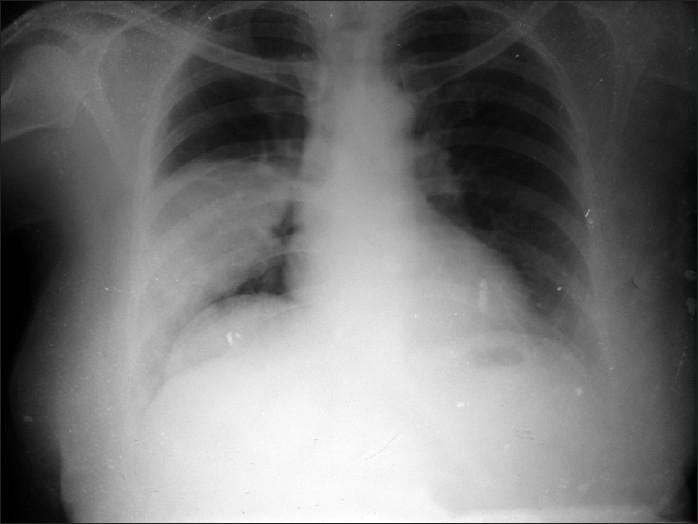

A 60-year-old female presented with pneumonitis of right lower zone. CT scan revealed mass like lesion with multiple air pockets. FNAC and ultrasound confirmed the diagnosis as isolated active pulmonary hydatid cyst, which is not common finding in adult population.

一名60岁女性因右下叶肺炎就诊。CT扫描显示有一个伴有多个气腔的肿块样病变。细针穿刺抽吸活检(FNAC)和超声检查确诊为孤立性活动性肺包虫囊肿,这在成人中并不常见。